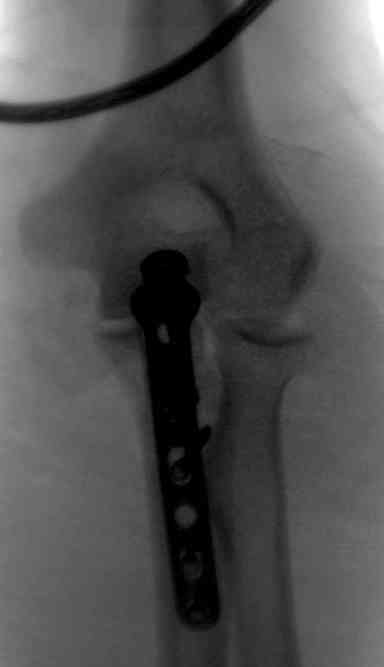

Для фиксации перелома локтевого отростка на сегодня множество преконтурных с блокирующими возможностями пластин.

Стабильную фиксацию, особенно при оскольчатых

переломах, можно добиться, применяя технику Bridge Plate, и за счет тех пластин, где имеется возможность проведения множественных шурупов (2.7 мм) проксимально.

Здесь выставлены несколько случаев и варианты фиксации локтевого отростка, некоторые в комбинации с другими переломами.

1 вариант применен ACUMED локинг пластина

2 вариант

перелом локтевого отростка с переломом головки лучевой кости (использованы 2 мм шурупы)

3 вариант

перелом с capitelum humerus и проксимальной трети улна